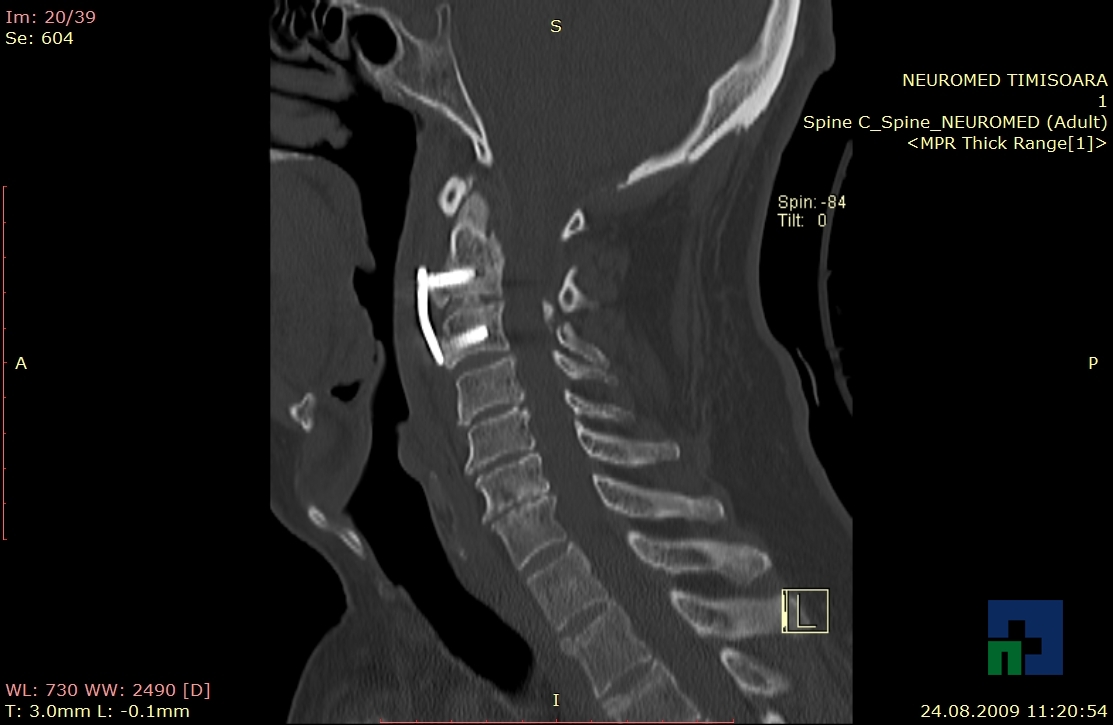

În cazul traumatismelor cranio-cerebrale:

- Diagnosticul edemului cerebral, a contuziei cerebrale, a leziunilor axonale difuze edematoase/hemoragice, a dilacerării cerebrale, a hematomului intraparenchimatos posttraumatic, a hematoamelor subdurale/extradurale (acute, subacute, cronice), a hemoragiei intraventriculare, a hemoragiei subarahnoidiene

- Diagnosticul traumatismelor de bază de craniu